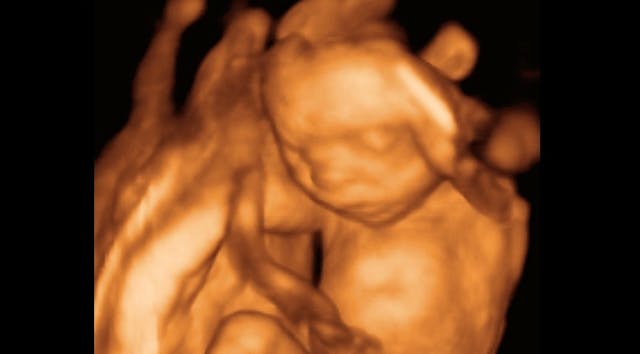

At 20 weeks, pain receptors are present throughout the baby’s body, and nerves are able to link these receptors to the baby’s brain. The baby can be seen reacting to stimuli that could be recognized as painful, by doing things like recoiling. Increases in stress hormones can be seen when the baby experiences painful stimuli. And while the abortion lobby tries hard to dismiss this as junk science, the reality is that it is just the opposite. In fact, doctors who perform fetal surgery use anesthesia on a routine basis – why would this be necessary if the baby could not feel pain?

The vast majority of people recognize the humanity of the preborn baby at 20 weeks. By 20 weeks, the baby can hear noises and recognize his mother’s voice. The baby will actually react to loud sounds, and noises that she becomes accustomed to hearing in the womb will be soothing to her when she is born. Other sensory development takes place as well – all five senses are being developed in the baby’s brain. And by 20 weeks, most women have already been able to feel their baby kicking and moving. The baby has also started swallowing, and her body begins producing meconium.